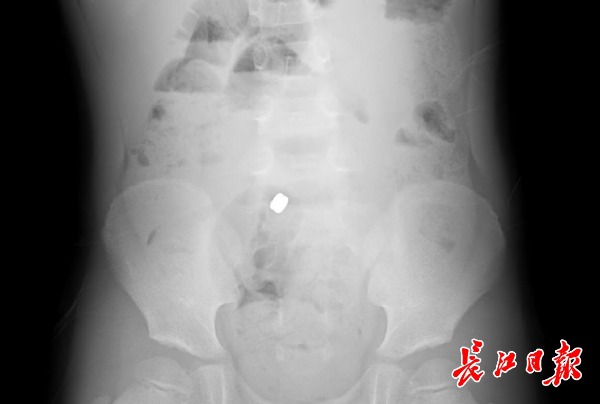

拍片显示,索索体内,两粒磁铁紧紧粘贴在一起。通讯员张祖国 摄

男孩小名叫索索(化名),还在上幼儿园大班。5月17日、18日两天,他放学回家都说肚子疼。妈妈吴女士担心他是消化不好,去家附近医院开了点药。但吃药后索索的情况仍未得到缓解。复诊时,医生问他有没有吃过什么东西,索索一直回答没有。幸亏医生多留了个心眼,建议家长带孩子拍片,结果证实索索体内有异物。

看着片子,索索才想起来自己吃过东西。他告诉妈妈,17日中午在幼儿园睡午觉,他闲得无聊,正好手里有从玩具上抠下的两颗小磁铁片,就放到嘴里尝味道,然后磁铁就滑进了肚子,索索很快就忘了这事。

听了儿子的话,吴女士吓坏了,连忙把他转到武汉儿童医院。进一步检查发现,索索体内的两颗磁铁在肠管内相互吸附,很危险。该院普外科一病区总住院医师孙烜与李欢医生立刻为索索做急诊腔镜手术,取出了磁铁。